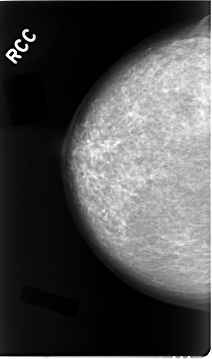

C_0023_1.RIGHT_CC

RIGHT_CC LINES 4664 PIXELS_PER_LINE 2744 BITS_PER_PIXEL 12 RESOLUTION 50 NON_OVERLAY